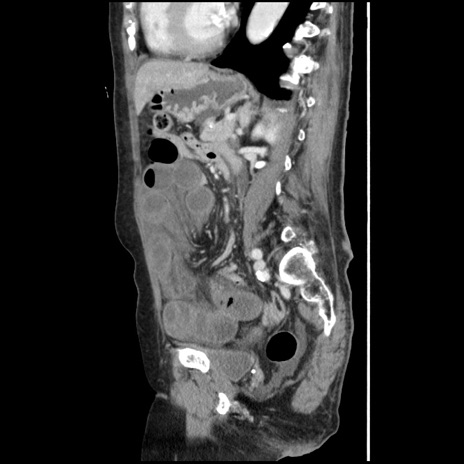

横断像

【症例】80歳代女性

【主訴】腹痛

【現病歴】8時間前から腹痛あり来院。

【既往歴】糖尿病、脂質異常症、子宮体癌にて子宮全摘術

【身体所見】意識清明・会話良好だが腹痛で苦悶様、全腹部にわたって反跳痛と圧痛あり

【データ】WBC 13600、CRP 0.14、LDH 224、CK 90